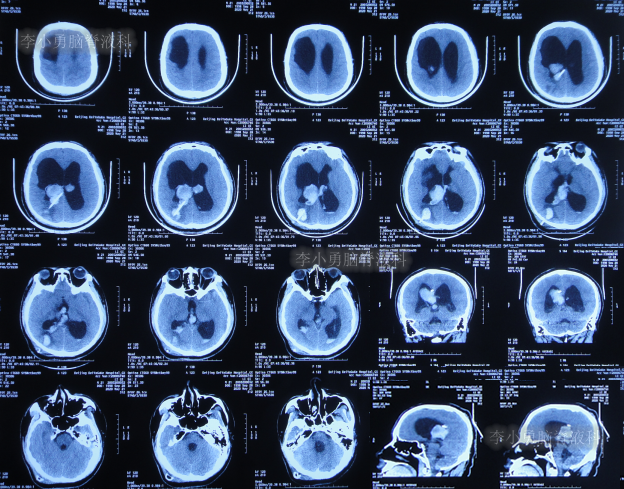

发现脑积水8年后即2013年9月16日,复查头颅CT示脑积水(图-1),没有相关症状,建议定期复查。

图-1:2013年9月16日头颅CT

发现脑积水11年即2016年7月20日,复查头颅CT(图-2)后,仍建议继续定期观察。

图-2:2016年7月20日头颅CT